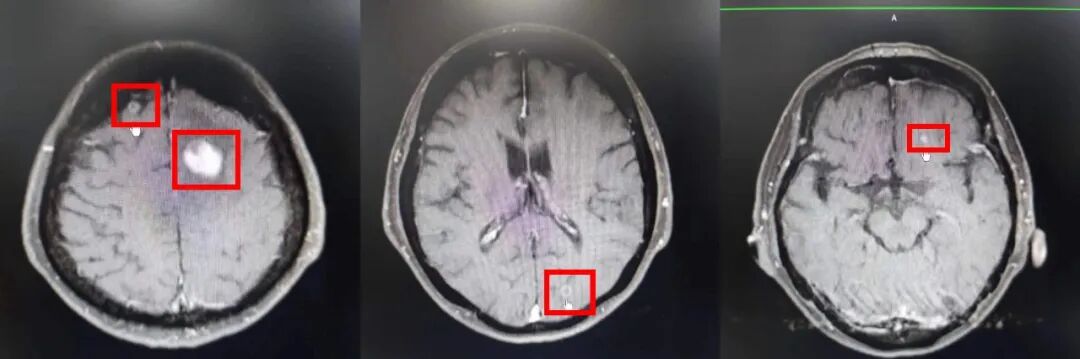

入院时,婆婆右侧上下肢活动障碍并进行性加重,完善颅脑增强核磁,核磁示双侧额叶、左侧枕叶多发占位性病变,部分伴瘤周水肿,结合病史考虑转移瘤。

图片

王婆最近一次颅脑增核磁